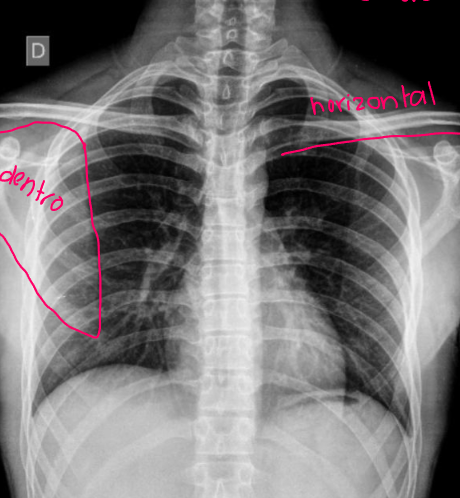

Esta es una radiografía de:

A

Describe el signo de la silueta (+)

¿En qué lóbulo está?

1 silueta (no se diferencia la de la lx de la del ♥️)

(lóbulo ↑)

¿Signo de la silueta?

Negativo

13

Q

Ubicación:

Positivo

Lóbulo superior

14

Lóbulo inferior

15